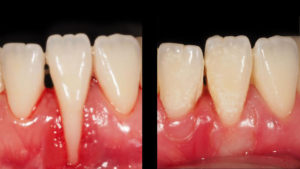

Cuando además de los síntomas de la gingivitis, se produce retracción de encías y/o perdida del hueso podemos afirmar que existe periodontitis. Si esta patología no la controlamos y la tratamos, el diente comenzará a moverse, apareciendo los famosos triángulos negros o huecos interdentales que tanto afectan a la estética. El paciente también puede sufrir molestias al masticar.

La pérdida de las encías es un problema doblemente grave, ya que afecta tanto a la salud bucal como a la autoestima por la apariencia estética. Las personas que sufren esta afección encuentran en la odontología, y en concreto en las técnicas de periodoncia, soluciones interesantes para esta situación.

Las encías retraídas tienen muchas causas asociadas, muchas son consecuencia de la falta de higiene dental o de hábitos poco saludables